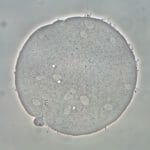

Sperm Penetration Assay (SPA)